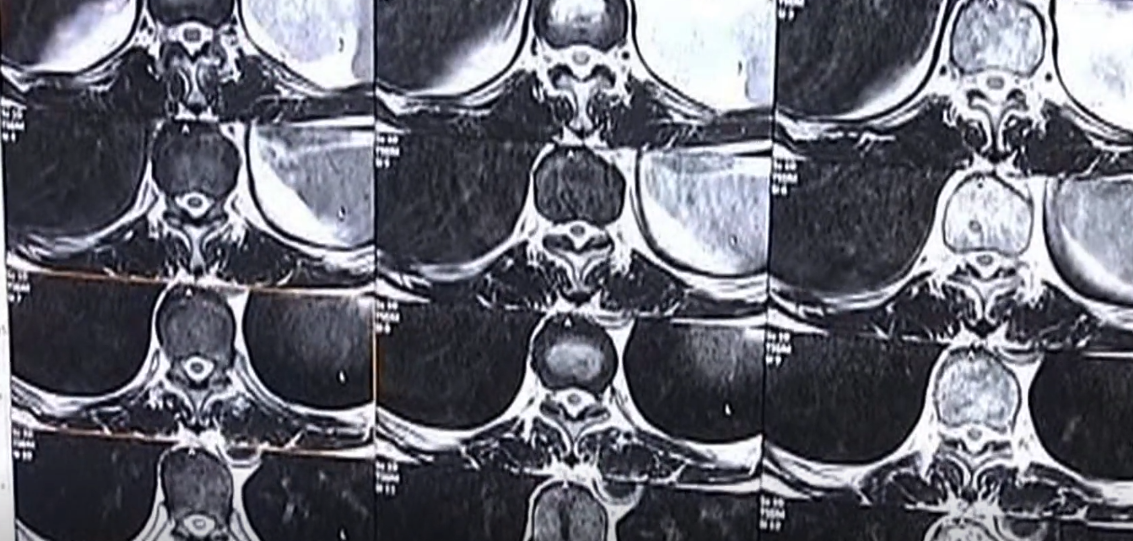

2012年12月,西南政法大学司法鉴定中心出具了司法鉴定意见书。意见书显示:从张秀银在郑州人民医院入院时所做的“左膝核磁共振描绘图”可以看出,当时她的左膝前交叉韧带存在新的损伤,而医院并没有记录在病例中。